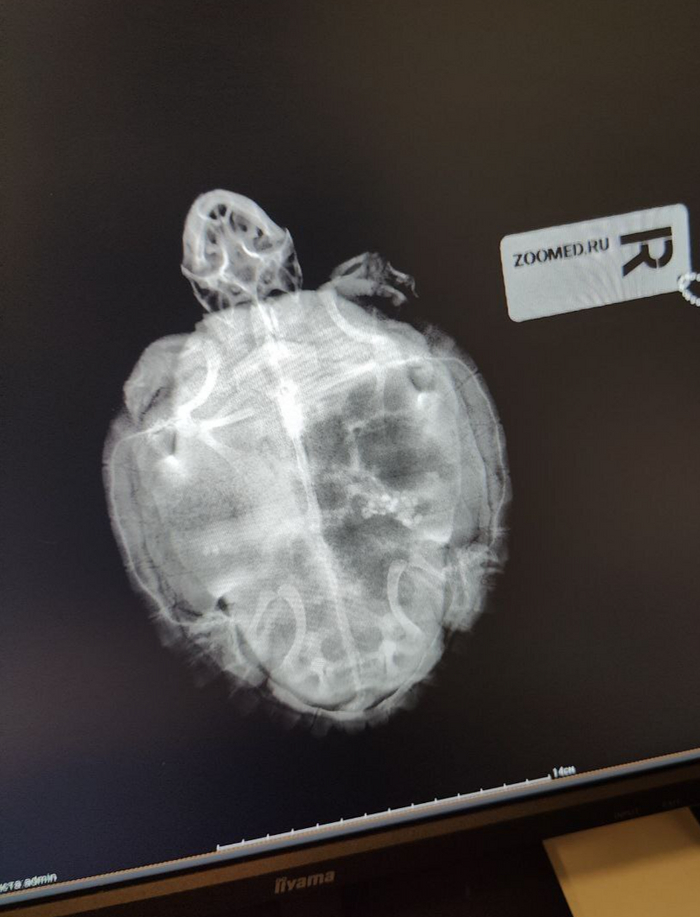

Перебирала старые снимки и наткнулась на фотографии, где я проводила рентген черепахе (у нее пневмония). И хотя я не являюсь специалистом по экзотическим животным, но рентген сделать смогу.

Пластырь для создания иллюзии фиксации :)